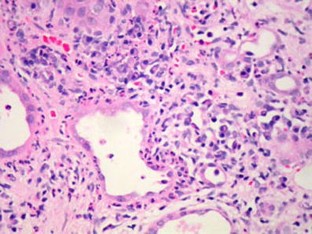

Fig. 2

We describe two adolescents who presented with end-stage renal failure and clinical features suggestive of Sjögren’s syndrome (SS). They both demonstrated severe, chronic, tubulointerstitial inflammation on renal biopsy, high-titre antinuclear antibodies, high immunoglobulin A and G concentrations, positive anti-SSA and anti-SSB antibodies, and negative anti-double-stranded DNA antibodies. One had subjective and objective evidence of the sicca complex (dry eyes and/or dry mouth) and fulfilled the commonly accepted SS consensus criteria. The other showed no evidence of the sicca complex but fulfilled modified criteria for juvenile SS. SS may be underrecognised as a cause of end-stage renal failure in childhood.